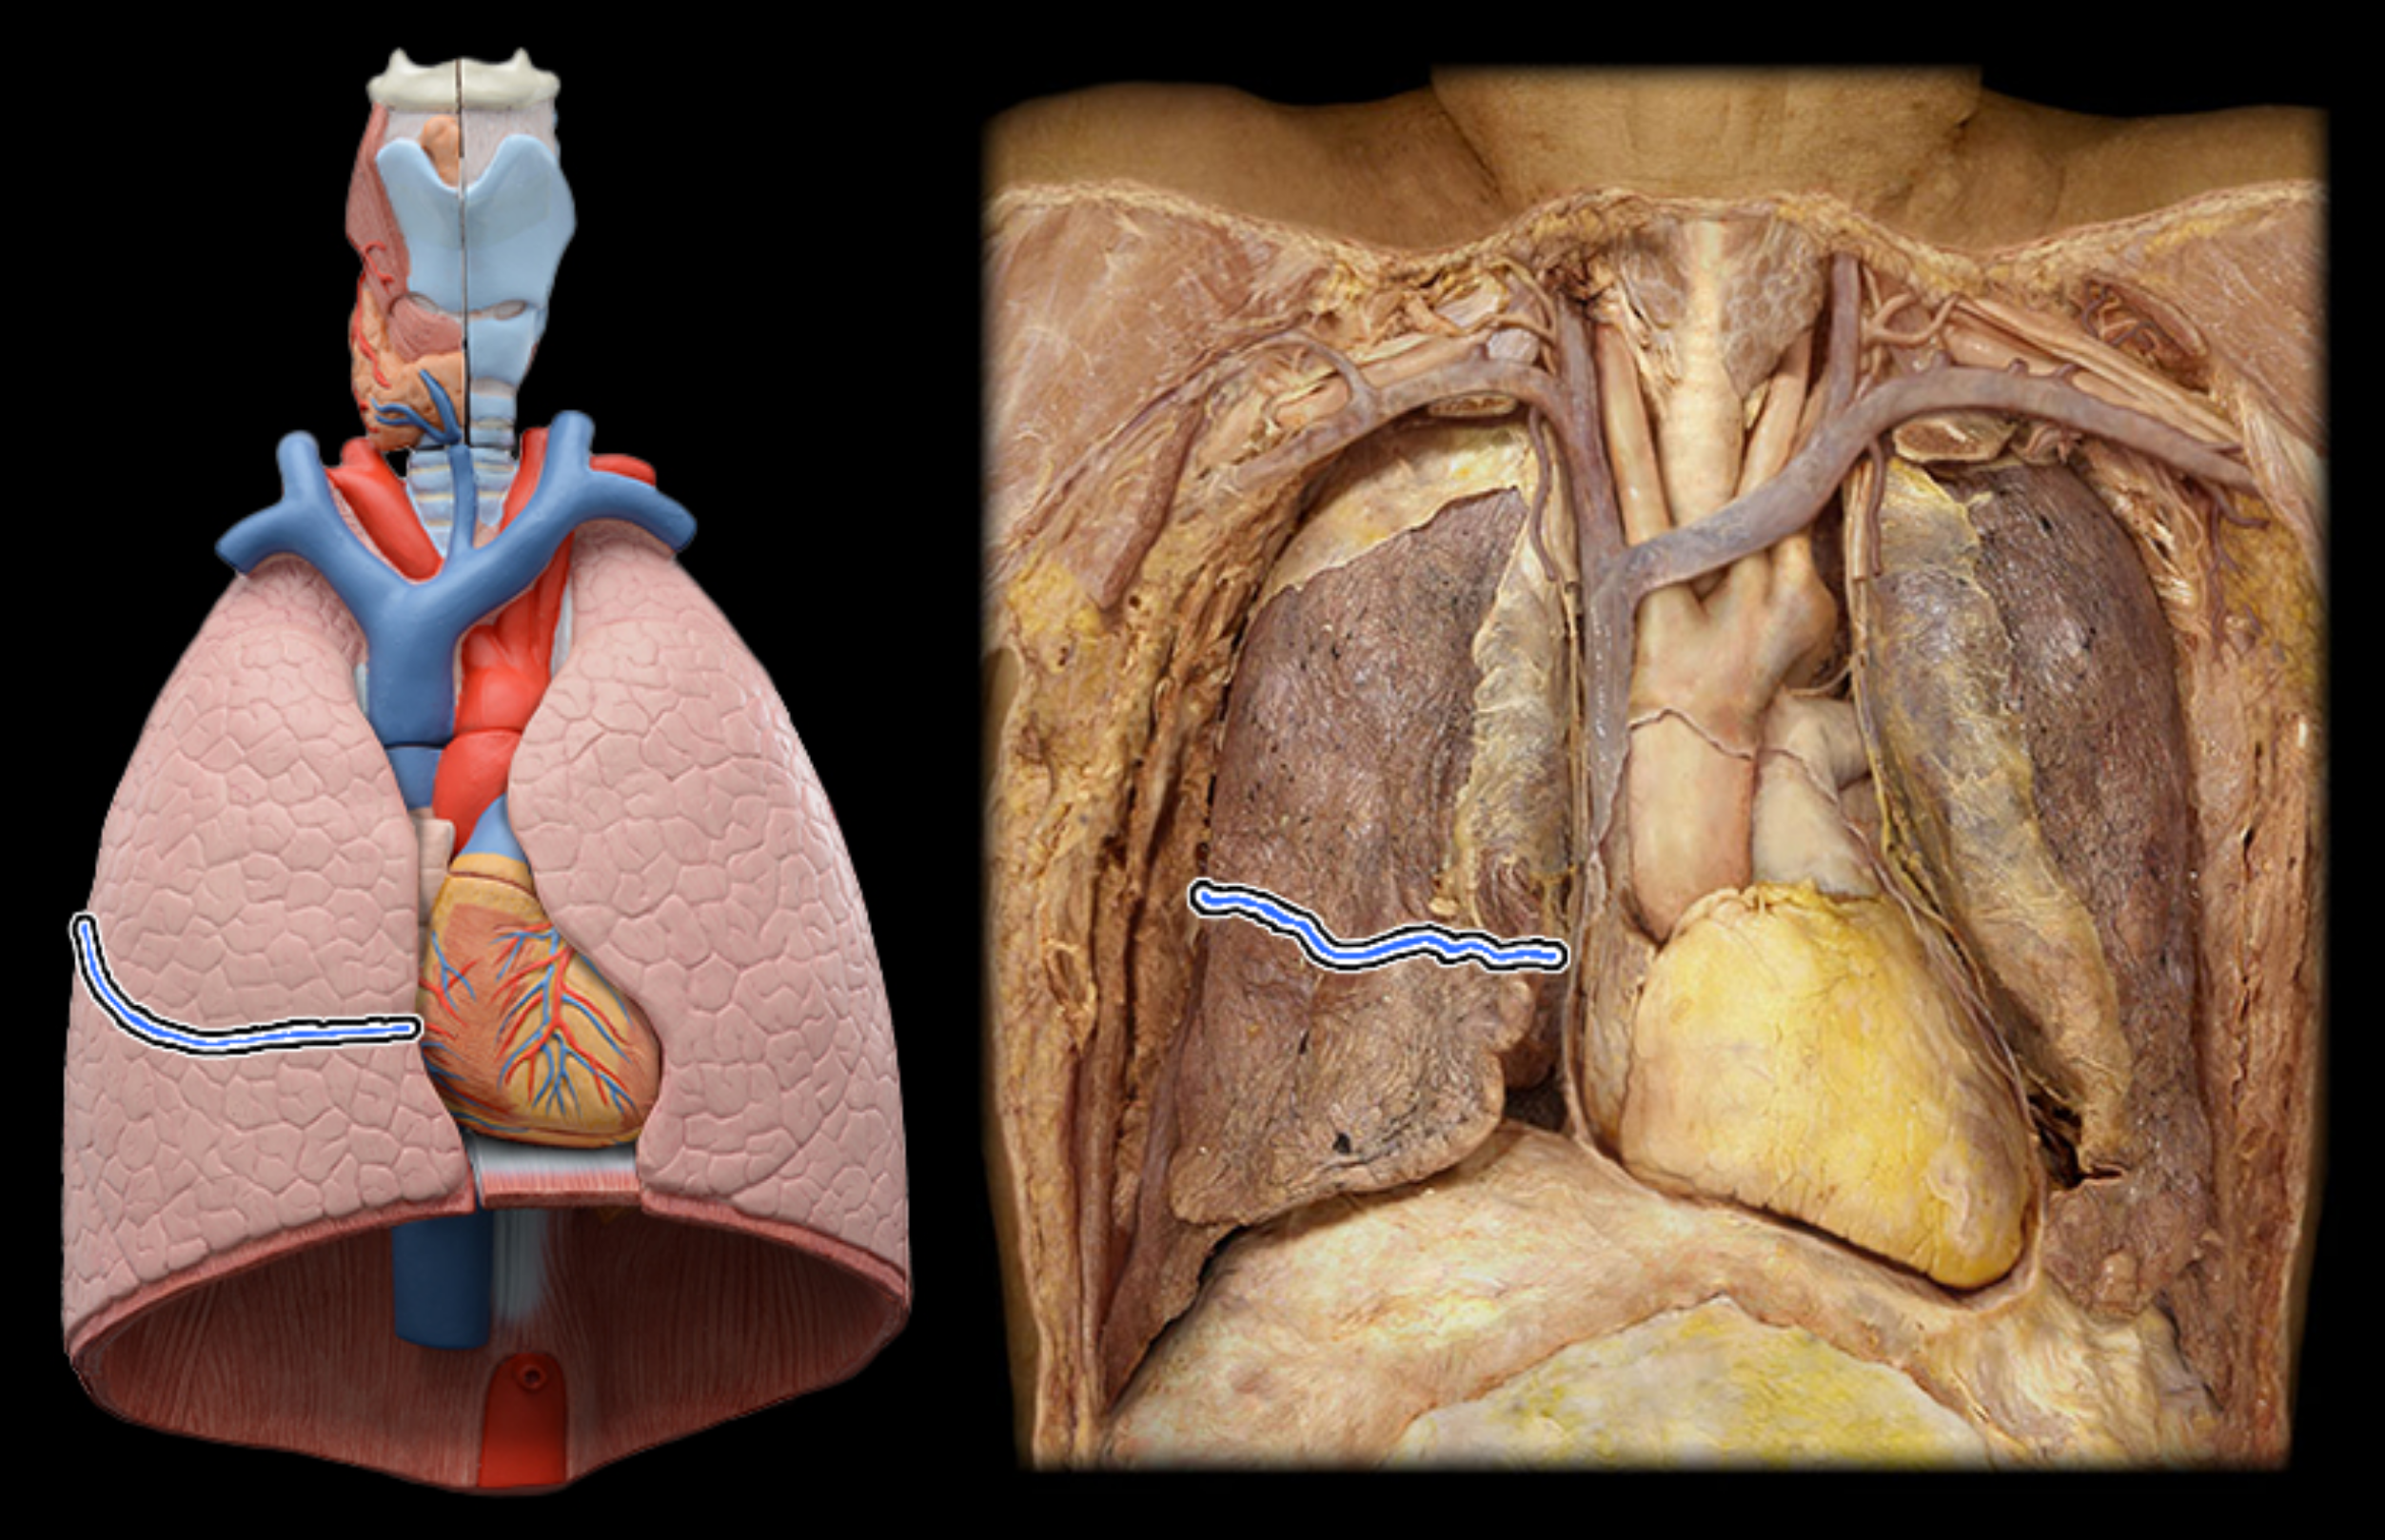

Superior, lobe of right lung

middle lobe of right lung

inferior lobe of right lung

Horizontal fissures of right lung

oblique fissures of right lung

Superior lobe of left lung

inferior lobe of left lung

oblique fissure of left lung

cardiac notch